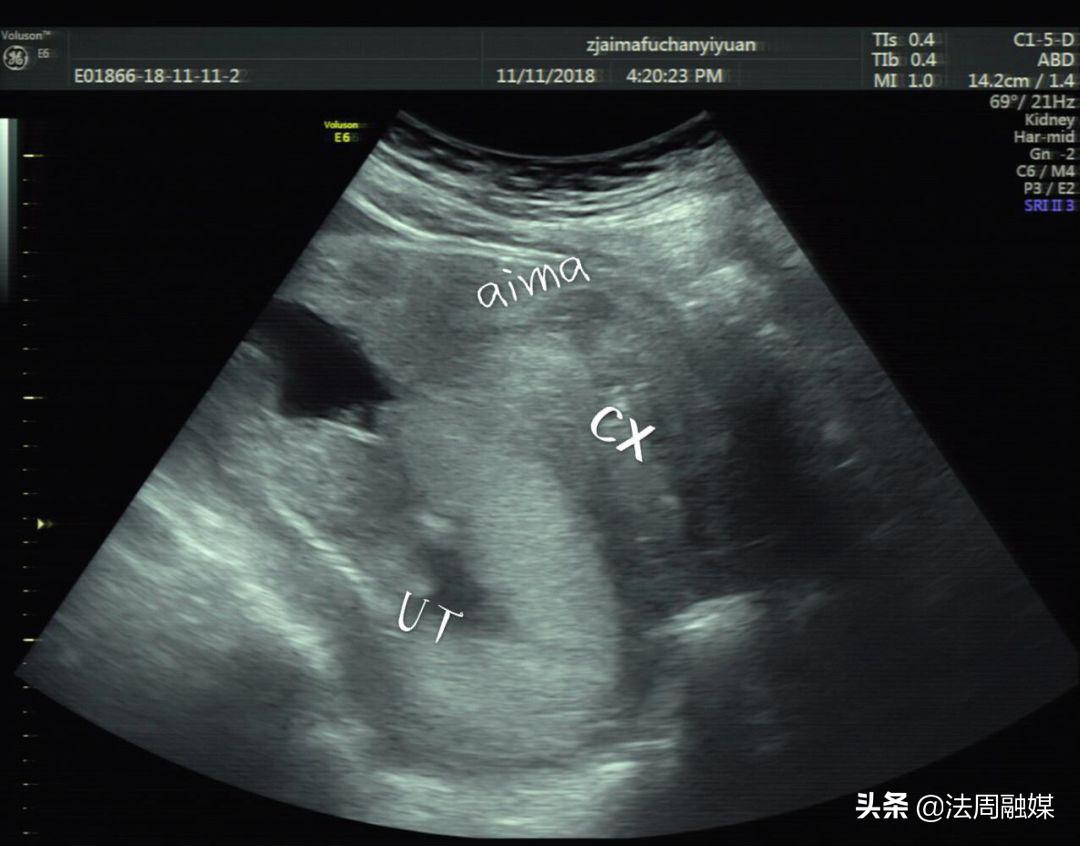

时间回到前一天。4月5日上午,何女士起床后发现自己排尿困难,并且下腹持续性胀痛,在丈夫的陪同下,夫妻俩来到常德市妇幼保健院就诊。孕产保健科主任杨御华见何女士左手按着下腹部且面色艰难,便优先接诊了何女士。经检查后怀疑是“尿潴留”,迅速开具了B超单并标明加急,第一时间为何女士安排了B超。经超声影像科童立里副主任医师B超检查:膀胱过度充盈,子宫明显后倾后屈位,宫内见胎儿回声,胎心胎动存在。确诊子宫箝闭症。

膀胱明显充盈表现细长,后方见妊娠子宫回声

子宫明显后倾后屈,宫颈细长